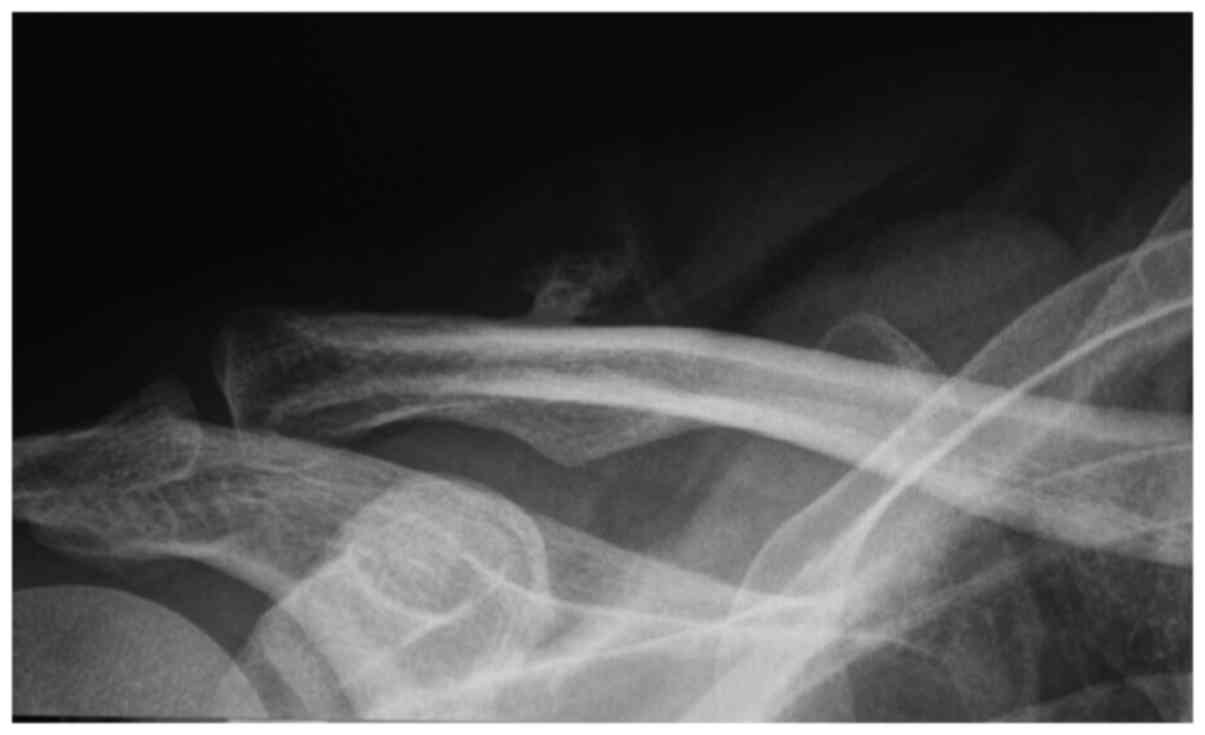

Radiographic examination revealed that the mass was located in the middle of clavicle, and its base intensity was similar to that of the clavicle; thus, the mass was initially suspected to be an osteochondroma (Fig. 1). On magnetic resonance imaging (MRI), the mass consisted of 3 layers (Fig. 2): The surface was encased in adipose tissue and the middle layer was osseous tissue; the base was fixed to the clavicle, but was not associated with clavicular marrow cavity. On T1- and T2-weighted images, the surface adipose tissue exhibited a high signal, while the core bone tissue exhibited a low signal.

Figure 1.

Plain radiograph of the right clavicle (front view) showing a well-defined radiolucent mass adjacent to the lateral aspect of the right clavicle. An irregularly-shaped, smoothly marginated osseous excrescence is seen within the radiolucent mass, attached to the cortex of the clavicle. No bone destruction was detected.

Parosteal lipoma may occasionally be misdiagnosed as osteochondroma, when there is association with the underlying bone (12). In this case, the X-ray examination raised the suspicion of osteochondroma. On MRI, the mass was characterized by high signal intensity on T1-weighted images, with low signal of the bone layer. The mass exhibited low signal intensity on T2-weighted images (Fig. 2).